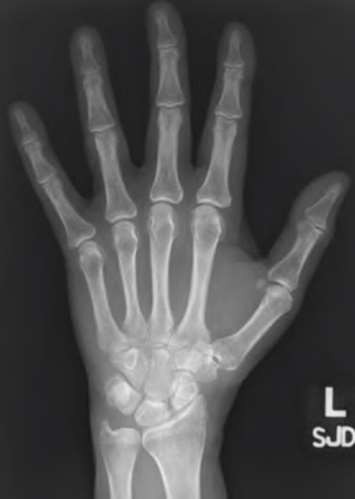

A 20-year-old park ranger trips and falls onto his right wrist with the wrist in extension and pronation. The local urgent care orders both radiographs and a CT, which you review and determine to be normal. The patient complains of ulnar-sided wrist pain. On exam, his tenderness is localized to the fovea. Ulnar deviation also causes him pain. There is no snapping sensation with wrist supination, flexion, and ulnar deviation. He otherwise has 5/5 strength to his first dorsal interosseous muscle with 4mm static two-point discrimination on the ulnar side of the 4th digit. Which of the following injuries is most likely responsible for his symptoms and exam?